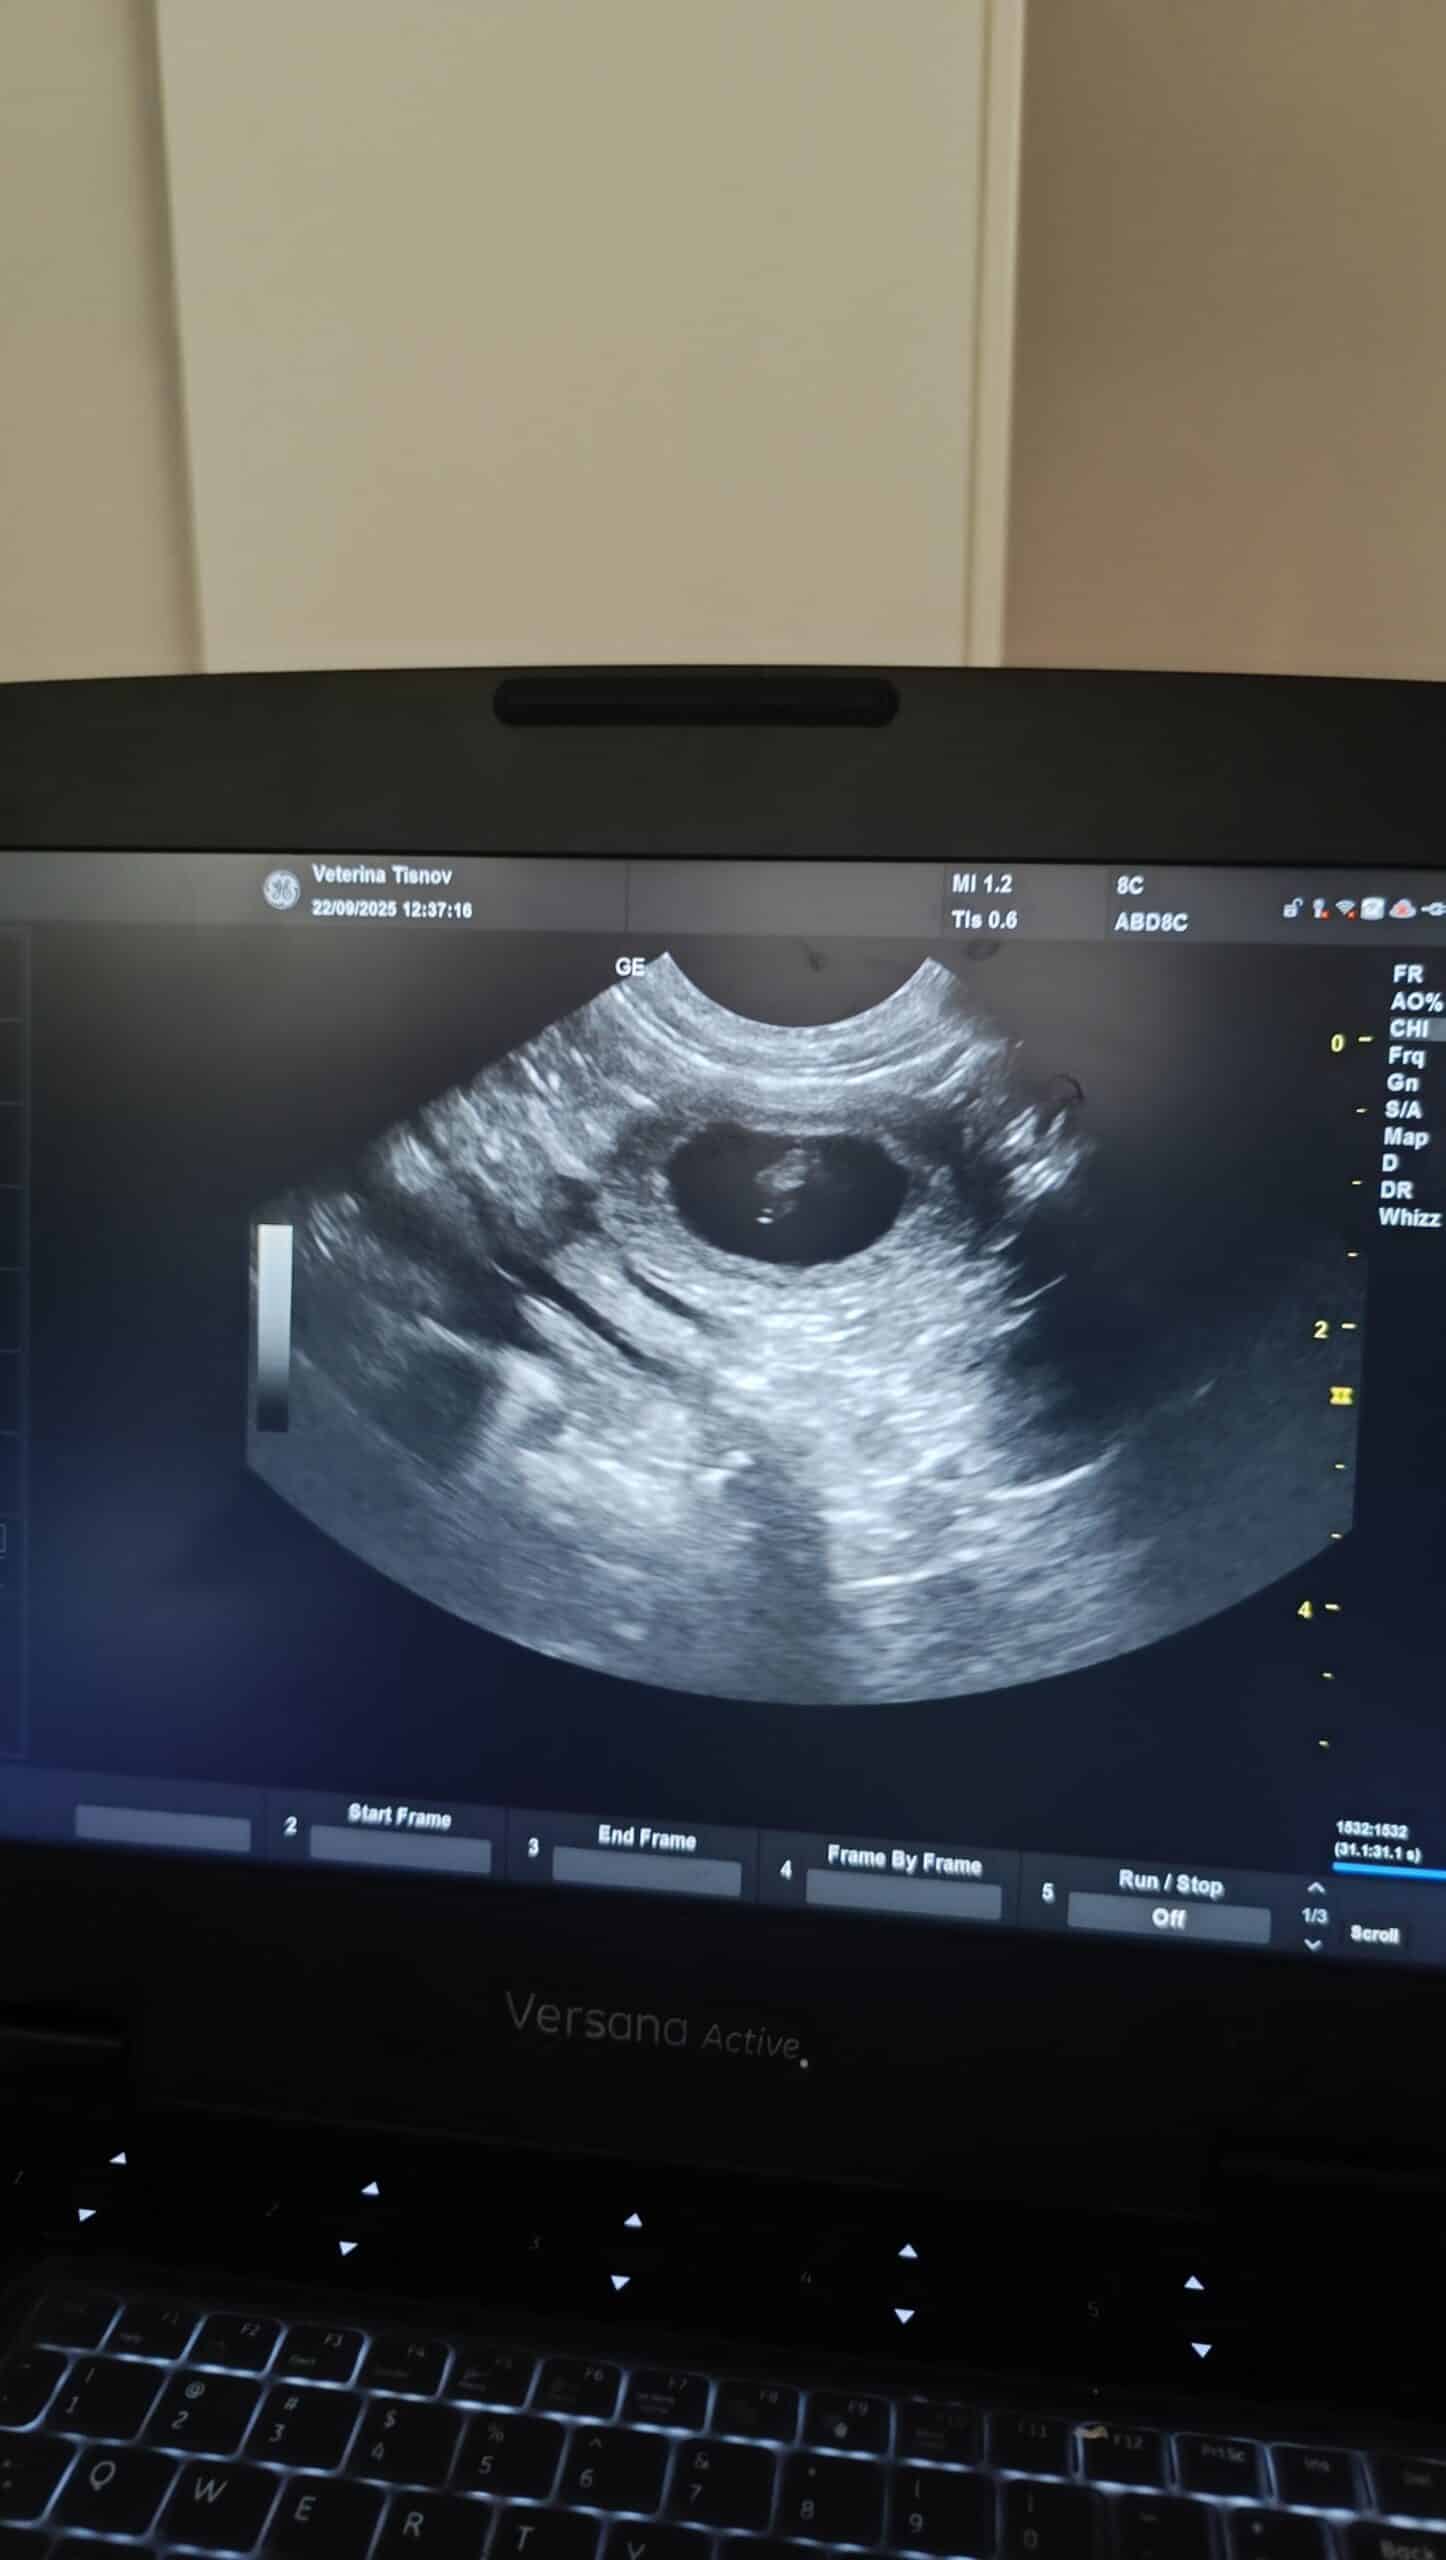

Šteniatka border kólie už túto jeseň 2025. Áno, je to tak. Sono dopadlo úspešne a ukázalo nám to, čo sme už všetci aj tak tušili. Maisynka je tehotná a krytie so Solom na konci augusta sa vydarilo. Na konci októbra/začiatkom novembra sa môžeme tešiť na malé guličky.

Maisynka sa má k svetu a tehotenstvo je na nej už vidieť.